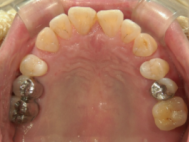

症例写真

症例写真(レントゲン)